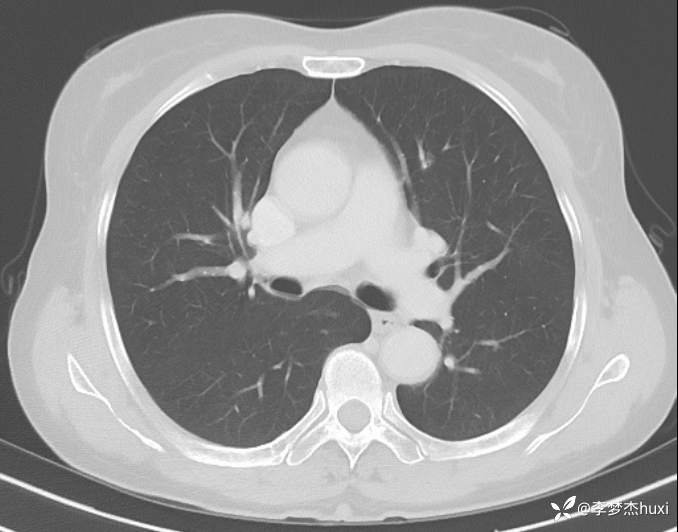

1.现病史:患者老年 女,患者于入院前3天(2024-06-02)体检查胸部CT:左肺部分实性结节,右肺磨玻璃结节,左肺上叶实性结节--性质?建议肺结节门诊会诊检查;双肺索条,双肺下叶条絮状高密度影--考虑肺血坠积效应,主动脉壁钙化,双侧胸膜局部增厚,左侧乳腺钙化点。2024-06-04查胸部增强CT:左肺上叶实性结节--占位?建议结合病理;左肺部分实性结节,右肺磨玻璃结节,建议肺结节门诊会诊检查;双肺索条,主动脉壁钙化,双侧胸膜局部增厚,左侧乳腺钙化点。患者目前无咳嗽、咳痰,无发热,无胸痛,今为求进一步诊治来我院,门诊以“肺诊断性影像异常”收入院。

4.辅助检查:2024-06-02查胸部CT:左肺部分实性结节,右肺磨玻璃结节,左肺上叶实性结节--性质?建议肺结节门诊会诊检查;双肺索条,双肺下叶条絮状高密度影--考虑肺血坠积效应,主动脉壁钙化,双侧胸膜局部增厚,左侧乳腺钙化点。2024-06-04查胸部增强CT:左肺上叶实性结节--占位?建议结合病理;左肺部分实性结节,右肺磨玻璃结节,建议肺结节门诊会诊检查;双肺索条,主动脉壁钙化,双侧胸膜局部增厚,左侧乳腺钙化点。。